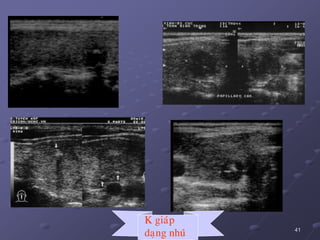

a/. Car. daïng nhuù: 75-90%, tieân löôïng toát, moät hay ña oå,

nhaân phaùt trieån raát chaäm, di caên xa hieám vaø di caên haïch sôùm

(aùi haïch). Laø ung thö giaùp duy nhaát ôû treû em, nöõ > nam. 1 soá

tröoøng hôïp coù haïch coå di caên do ung thö giaùp nhöng khoâng

thaáy nhaân giaùp treân ñaïi theå vaø SA. Khi nhaân kích thöôùc lôùn,

thuøy coøn laïi deã bò ung thö neân caàn caét giaùp gaàn troïn.

 86,7% laø nhaân ñaëc echo keùm, khi lôùn hôn 1 cm nhaân trôû

neân khoâng ñoàng nhaát, giôùi haïn khoâng roõ, 50% coù vi voâi hoùa,

ít thaáy ñöôïc hình daïng nhuù trong nang.

K giaùp

daïng nhuù

 Ñaëc ñieåm haïch di caên: maát hình baàu duïc, thöôøng hình

troøn, khoâng coøn roán haïch echo daày ôû vuøng trung taâm duø

haïch kích thöôùc nhoû. Ñoâi khi haïch coù caáu truùc echo daày

hôn cô, ñoàng nhaát, hay hoaïi töû, coù theå coù vi voâi hoùa trong

haïch. Ñoâi khi haïch mang hình aûnh gioáng nhö nhaân ung

thö nguyeân phaùt cuûa TG.

THuøy P

THuøy T

Haïch

coå phaûi